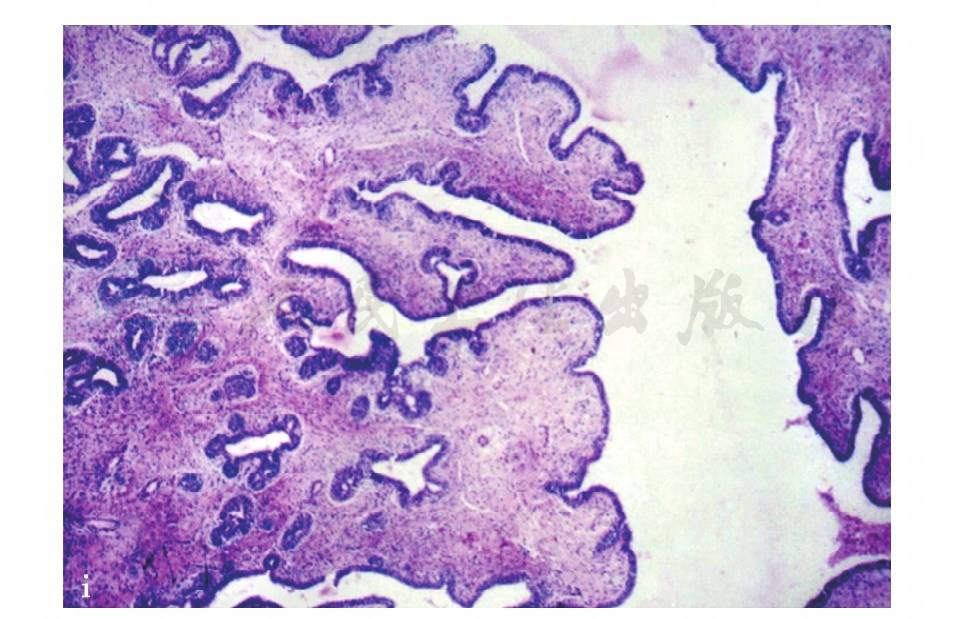

图19 c,病理示镜下可见导管上皮增生呈乳头状